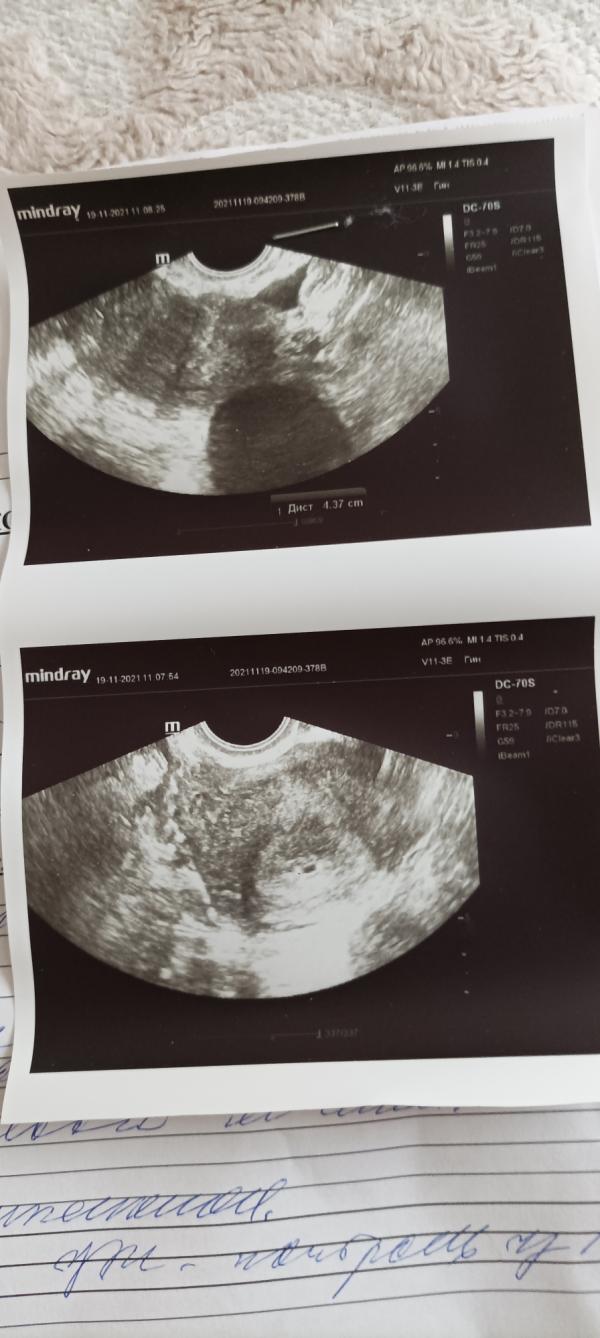

Не выдержала , сходила на узи . плод в матке ❤️какая то киста врач не сказала , что за киста ...

У меня тоже киста желтого тела на яичнике это нормально в беременность, надо наблюдать чтоб не росла просто :)

Киста жёлтого тело поддерживает беременность именно желтое тело вырабатывает прогестерон. Это хорошо, что оно есть, с вами будет до 16 недель пока полностью не сформируется плацента.

Спасибо ,Полгода назад , ничего не было .... Ещё странно то , что в другие беременности не говорили про кисту , а сегодня врач сказала может это желтое тело , может и нет

Киста желтого тела? Это киста после овуляции